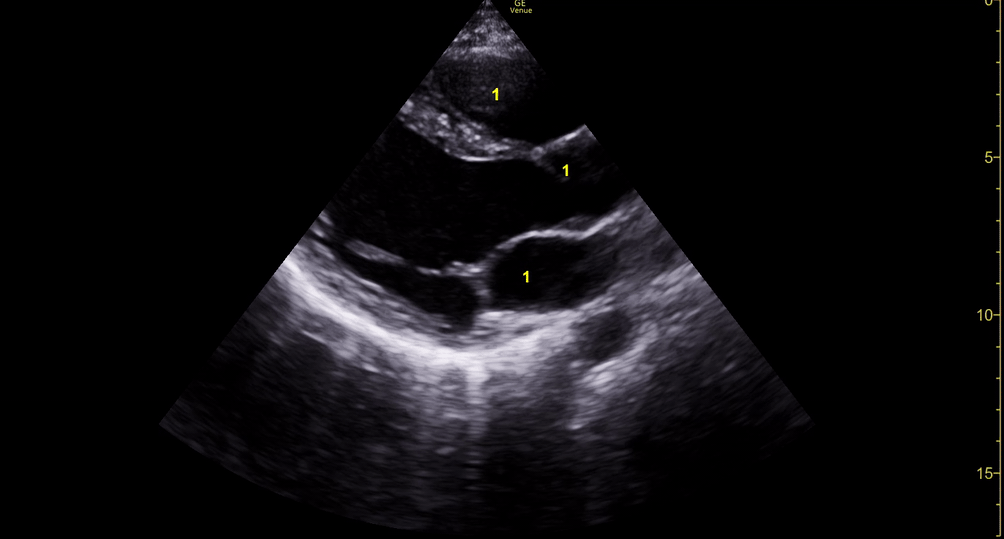

Depiction of E-point septal separation: M-mode is used to measure the distance between the open mitral valve and the ventricular septum. Measurements greater than 7 mm are suggestive of depressed systolic ejection. (1. RV free wall, 2. Interventricular septum, 3. Mitral valve, 4. LV free wall). From: The "5Es" of emergency physician-performed focused cardiac ultrasound (11).